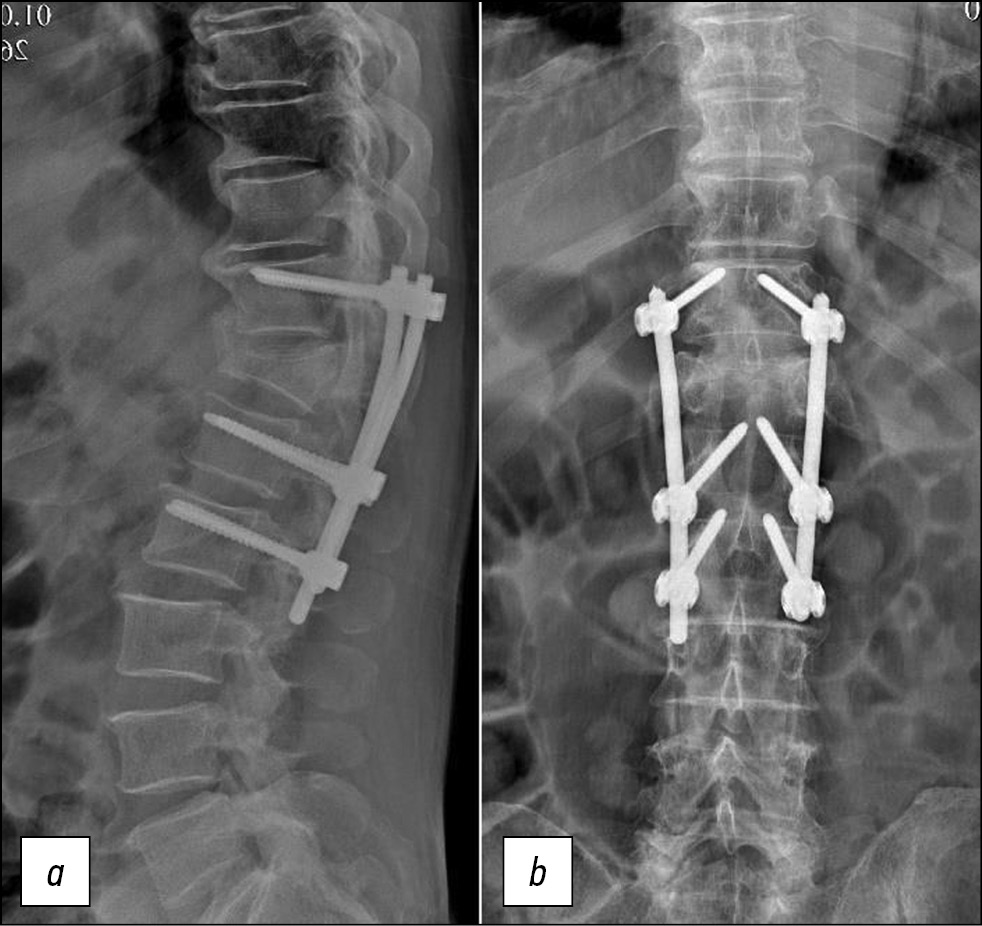

При контрольном осмотре и рентгенографии через 12 месяцев после операции потери коррекции и признаков нестабильности конструкции не выявлено (рис. 5). Неврологический статус без отрицательной динамики. Походка у пациента уверенная, дополнительной опоры не требуется, осанка не нарушена. Контрольное анкетирование: интенсивность боли в спине (ВАШ) — 0–1 балл (стоя=лежа), качество жизни (ODI) — 8%.

Рис. 5. Рентгенограммы позвоночника больного Е., 72 года, через 12 мес после операции, прямая (a) и боковая (b) проекции.